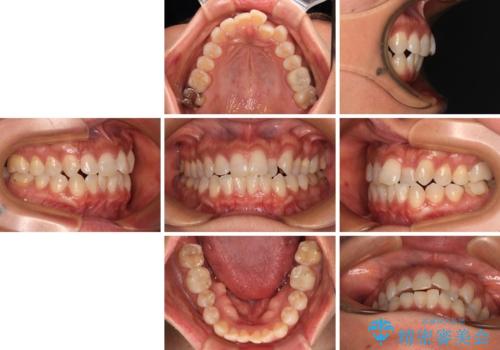

クロスバイトを治したい インビザラインによる矯正治療

- 前歯のクロスバイトを気にして来院された患者様です。

上下ともに、前歯部を中心にやや叢生が認められる程度であったため、ワイヤーでもインビザラインでも、どちらでも対応可能な状態でした。